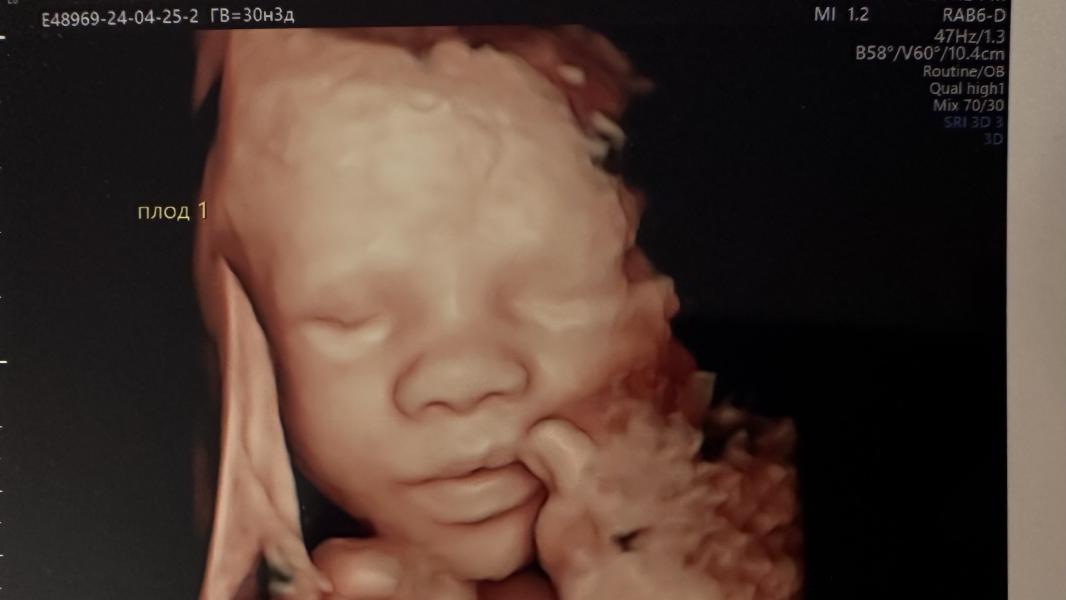

Сегодня была на последнем скрининге.

С малышами все хорошо 🙏🏻🙏🏻🙏🏻 Богатыри💪🏻 уже по 1,5кг💪🏻 девочку не удалось хорошо сфоткать как бы мы не старались😔 Прятала лицо, складывала на лицо ножки😁 а вот мальчики попозировали🫶🏻

Осталось совсем чуть-чуть, скоро увижу своих малышей❤️❤️❤️